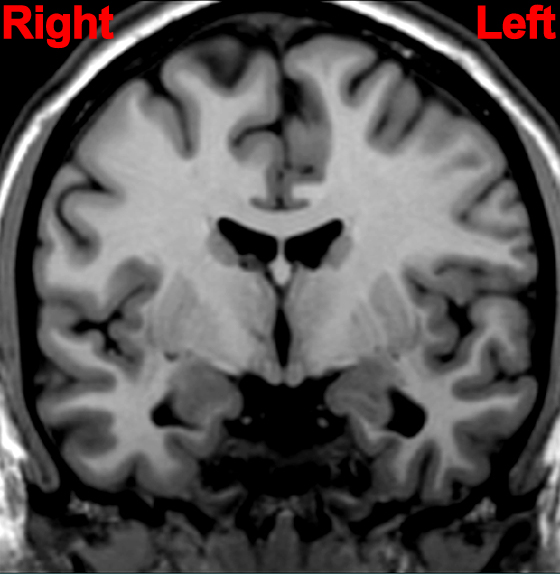

Locate a likely non-cortical site of a lesion for a patient with paralysis of the right side of the body and lower half of the face on the right side.